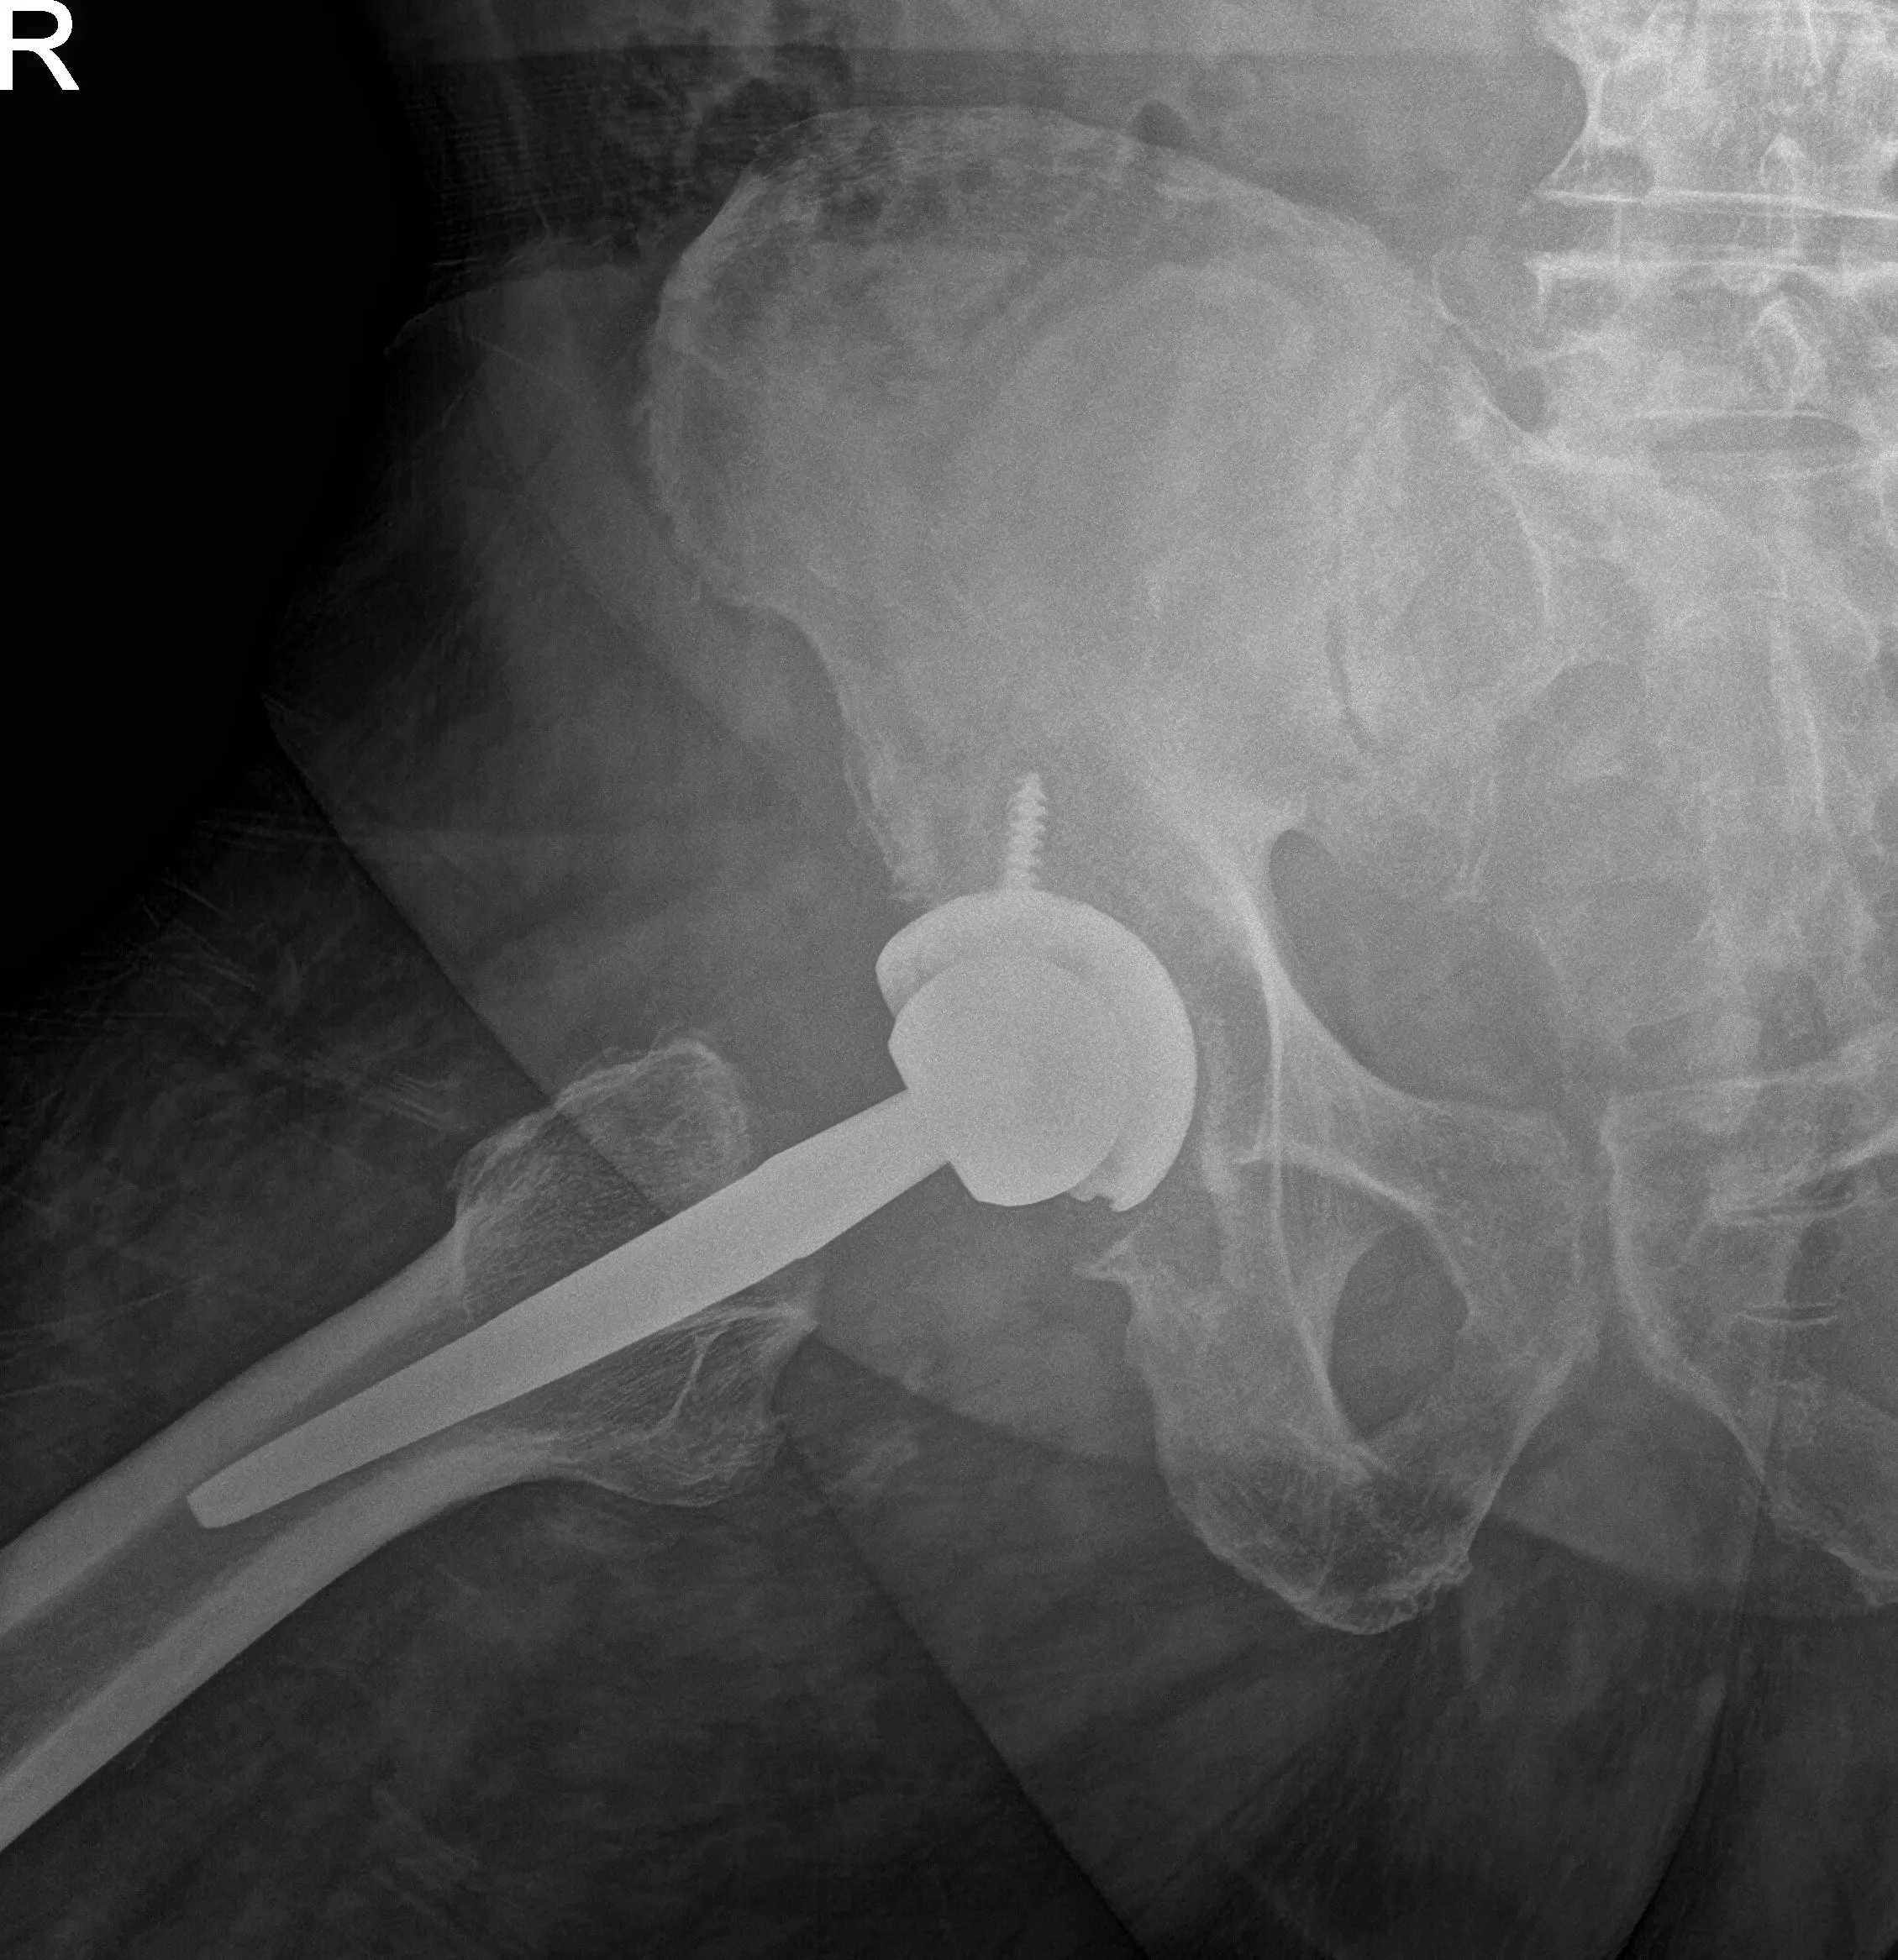

OPERATION: Right total hip arthroplasty.

IMPLANTS USED: 52 mm cup with 6.5 mm screw, 25 mm in length with a 0-degree polyethylene with a 127-degree neck stem with a ceramic femoral head 36 mm minus 2.5.

Neck resection was made at the correct level. Attention was then turned towards the acetabulum. The remainder of the labrum was then debrided. The acetabulum was then sequentially reamed. The final shell was then placed into position in the correct abduction and anteversion. A screw was used for additional fixation. A poly was then placed over the shell and attention was then turned towards the femur.

The femur was then sequentially broached. The final broach was left into position. The trunnion and the head were then placed over the stem. Lesser trochanter distance was measured and was found to be correct. The hip was then relocated. Trialed for a physiological range of motion.

There was no impingement. The stability was good. The hip was then dislocated. The trial components were then removed. The final components were then placed into position. The hip was then reduced. Thorough irrigation was given. Posterior soft tissue structures were then tagged to the greater trochanter through transosseous tunnels. The fascia was closed with Vicryl and Ethibond.